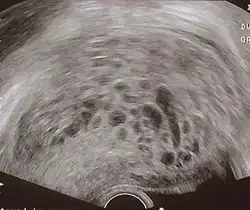

Transvaginal ultrasonography showing a molar pregnancy

Molar pregnancy in ultrasound

The diagnosis is strongly suggested by ultrasound (sonogram), but definitive diagnosis requires histopathological examination. On ultrasound, the mole resembles a bunch of grapes ("cluster of grapes" or "honeycombed uterus" or "snow-storm").[14] There is increased trophoblast proliferation and enlarging of the chorionic villi, and angiogenesis in the trophoblasts is impaired.[15]